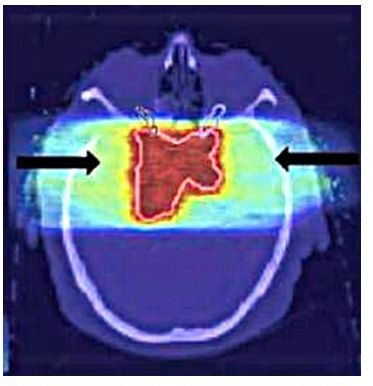

Abbildung 5: Eine CT-Aufnahme eines Gehirntumors (roter Bereich). Quelle: Mit freundlicher Genehmigung durch Katja Parodi und Walter Assmann: Haddronen gegen den Krebs, in Physik Journal 18(2019) Nr.6, Seite 39, Abb3.

Die Tumore innerhalb des Körpers können auch durch moderne Analyseverfahren wie die Computertomografie (CT) oder die Magnetresonanztomographie (MRT) (siehe Abb. 5) erkannt werden. Nur in wenigen Fällen wie beim Hautkrebs sind die dabei auftretenden bösartigen Tumore auch ohne Hilfsmittel sichtbar. Während die Tumore des Hautkrebses nur wenige mm bis zu einem cm tief im Gewebe liegen, kommen Tumore bis zu etwa 20 cm tief im Körper vor, wie man in der Abbildung 5 an der Lage des Tumors sehen kann.